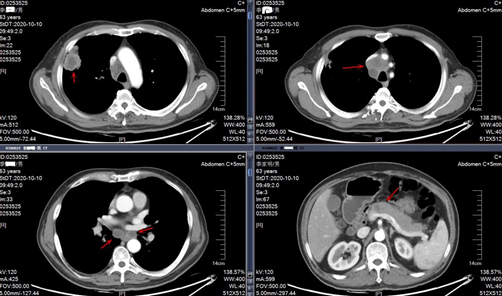

入院CT结果

2020-11-16CT结果

复查CT对比图